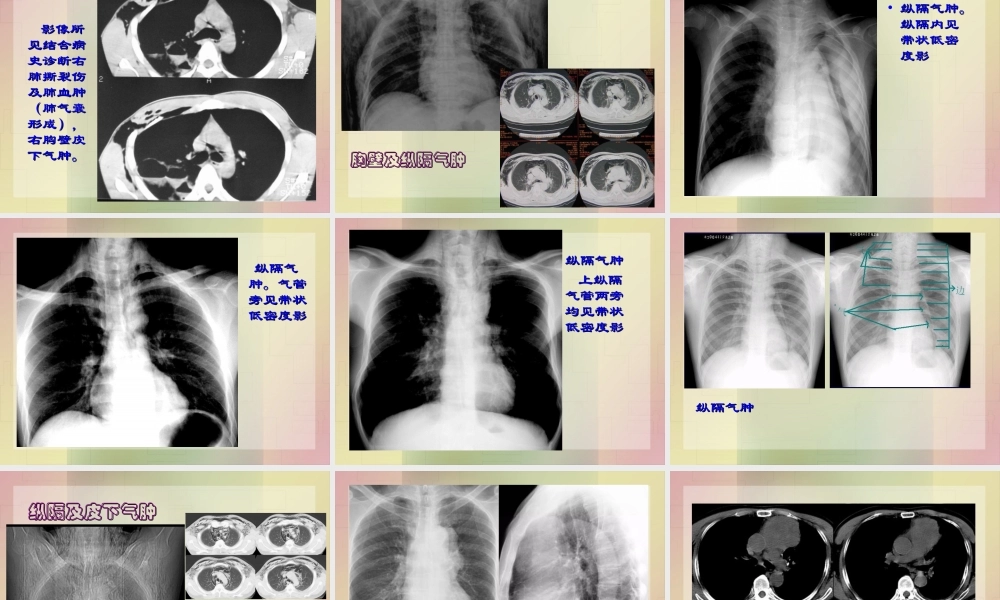

胸部外伤胸部外伤病理与临床病理与临床•肋骨骨折肋骨骨折比较常见,可为单发骨折,比较常见,可为单发骨折,也可为多发骨折,还可为单一肋骨也可为多发骨折,还可为单一肋骨的多处骨折。以的多处骨折。以3-103-10肋的腋部及背肋的腋部及背部多见。部多见。病理与临床病理与临床•肺挫伤肺挫伤是肺部常见的外伤性改变,是肺部常见的外伤性改变,可发生于外伤的着力部位,亦可为可发生于外伤的着力部位,亦可为对冲伤。主要病理改变为肺间质或对冲伤。主要病理改变为肺间质或肺实质内的液体渗出,多在外伤后肺实质内的液体渗出,多在外伤后66小时出现,小时出现,24-4824-48小时开始吸收,小时开始吸收,3-43-4天完全吸收。天完全吸收。病理与临床病理与临床•纵隔气肿和血肿纵隔气肿和血肿。。1.1.纵隔的直接穿纵隔的直接穿通伤;通伤;2.2.胸部闭合性外伤;胸部闭合性外伤;3.3.气气管及食管的破裂管及食管的破裂XX线表现线表现11.肋骨骨折本身.肋骨骨折本身•骨折线的存在及形状。骨折线的存在及形状。•对合情况。对合情况。22.继发征象.继发征象•气胸、液气胸、皮下气肿及纵隔气肿气胸、液气胸、皮下气肿及纵隔气肿3.3.脱位:多见于脱位:多见于1212肋与脊椎的关节,包括肋与脊椎的关节,包括肋椎关节及肋横突关节肋椎关节及肋横突关节XX线表现线表现肺挫伤肺挫伤11.肺纹理边缘模糊不清,失去正常锐利的.肺纹理边缘模糊不清,失去正常锐利的边界。边界。22.肺内还可以出现渗出性病灶,为肺泡内.肺内还可以出现渗出性病灶,为肺泡内渗出或出血。渗出或出血。XX线表现线表现11.纵隔气肿表现为纵隔两旁平行于纵隔的.纵隔气肿表现为纵隔两旁平行于纵隔的气带样影。气带样影。22.纵隔血肿量多时可见对称性纵隔增宽,.纵隔血肿量多时可见对称性纵隔增宽,或局限性软组织影。或局限性软组织影。•左侧多发肋左侧多发肋骨骨折,创骨骨折,创伤性湿肺。伤性湿肺。•左下肺创左下肺创伤性湿肺,伤性湿肺,左侧胸壁左侧胸壁皮下气肿。皮下气肿。•两侧胸壁两侧胸壁皮下气肿皮下气肿•左侧胸部左侧胸部术后,胸术后,胸壁皮下气壁皮下气肿形成肿形成•散弹枪伤,创伤性湿肺,颈部皮下气肿散弹枪伤,创伤性湿肺,颈部皮下气肿患者男,患者男,3737岁,外岁,外伤后右侧胸伤后右侧胸痛痛11天(被天(被锚挤压伤)。锚挤压伤)。患者除胸痛患者除胸痛外,无咳嗽、外,无咳嗽、咯血。患者咯血。患者否认“既往否认“既往肺部疾病肺部疾病史”。史...